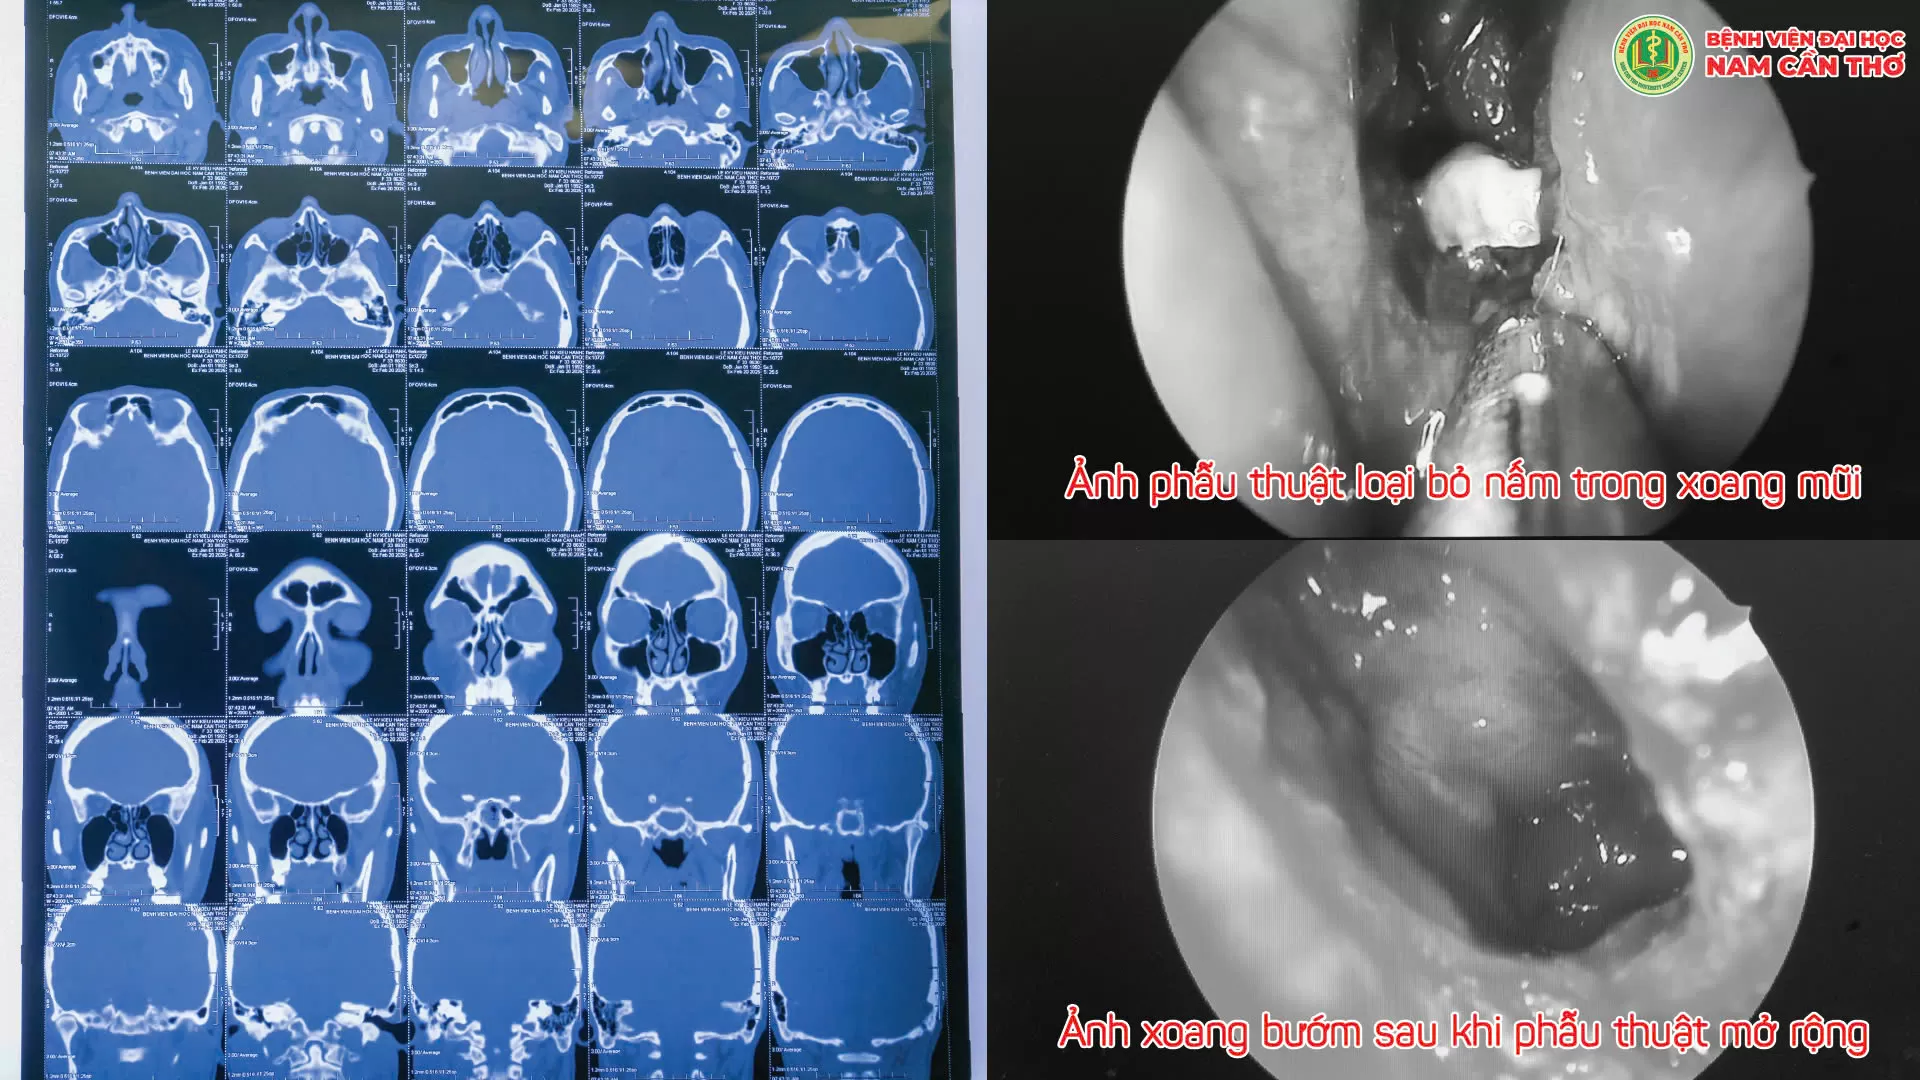

☘️Tại Khoa Mắt-TMH-RHM – Bệnh viện Đại học Nam Cần Thơ, các bác sĩ đã tiến hành thăm khám và thực hiện các xét nghiệm cần thiết. Bệnh nhân có các triệu chứng như nghẹt mũi, chảy mũi hôi, mũi có dịch nhầy và mủ đục ở ngách sàng bướm bên phải, họng đọng đờm. Kết quả chụp CT Scan cùng các triệu chứng cho thấy, bệnh nhân mắc bệnh viêm xoang bướm. Ngoài ra, hình ảnh chẩn đoán còn ghi nhận tình trạng viêm đa xoang, vẹo vách ngăn mũi sang trái, khí hóa cuốn mũi giữa hai bên của bệnh nhân, góp phần làm bệnh diễn tiến phức tạp hơn.

☘️Trước tình trạng bệnh phức tạp, BS.CKII. Vương Trương Chí Sinh cùng ekip đã tiến hành phẫu thuật mở xoang bướm cho bệnh nhân. Đây là một phương pháp phẫu thuật khá phức tạp, đòi hỏi độ chính xác và chuyên môn cao, do xoang bướm nằm sâu trong hốc mũi và gần các cấu trúc quan trọng như dây thần kinh thị giác và động mạch cảnh trong.

☘️Với sự tỉ mỉ và cẩn trọng trong từng thao tác, các bác sĩ đã loại bỏ ổ viêm, giải phóng dịch mủ ứ đọng trong xoang bướm, đồng thời cải thiện tình trạng thông khí của của hệ thống mũi xoang, mang lại hiệu quả điều trị tối ưu cho bệnh nhân. Ca phẫu thuật diễn ra thành công, hiện bệnh nhân đã hồi phục hoàn toàn và được xuất viện trở về cuộc sống sinh hoạt bình thường.